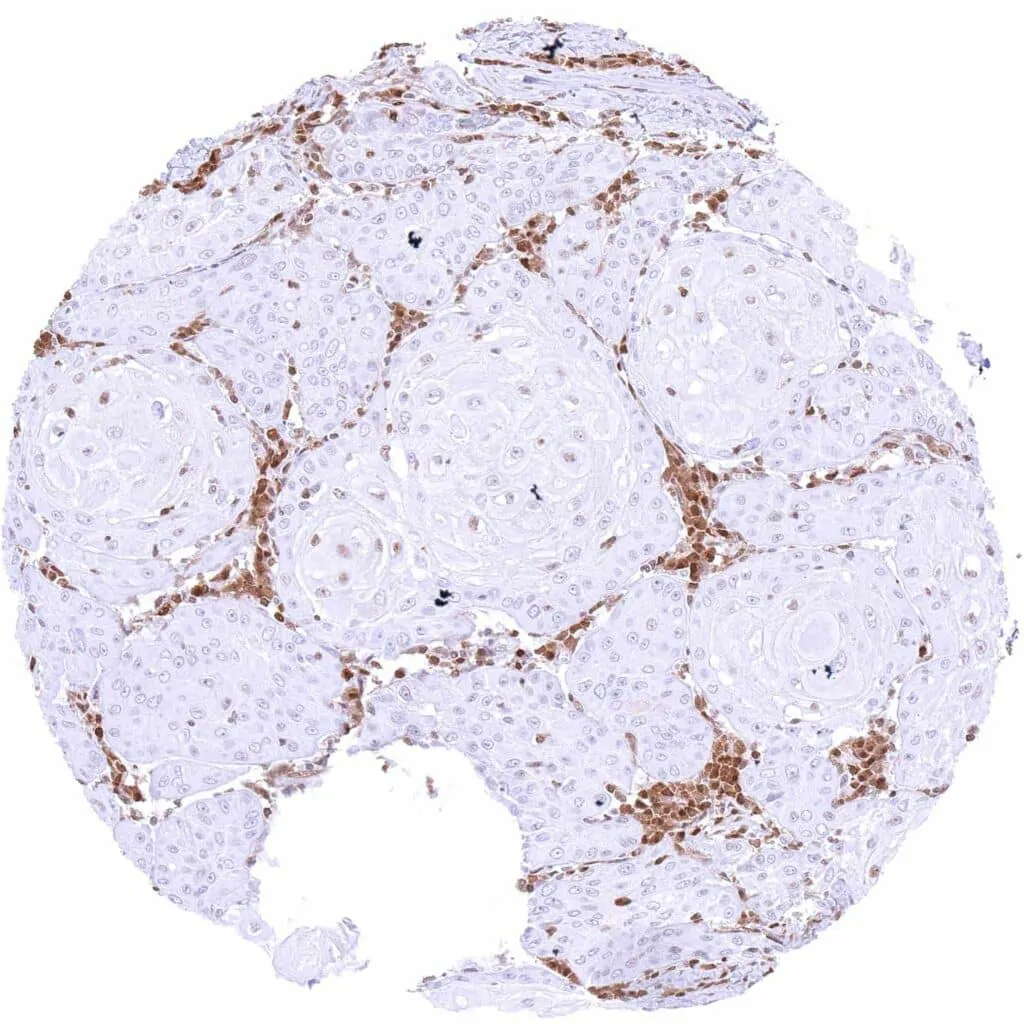

Kidney – Chromophobe renal cell carcinoma with distinct nuclear p27 staining of all tumor cells.

Kidney – Oncocytoma with weak to moderate nuclear p27 staining of tumor cells. A strong cytoplasmic and nuclear p27 staining is also seen in stroma cells (especially in endothelial cells).